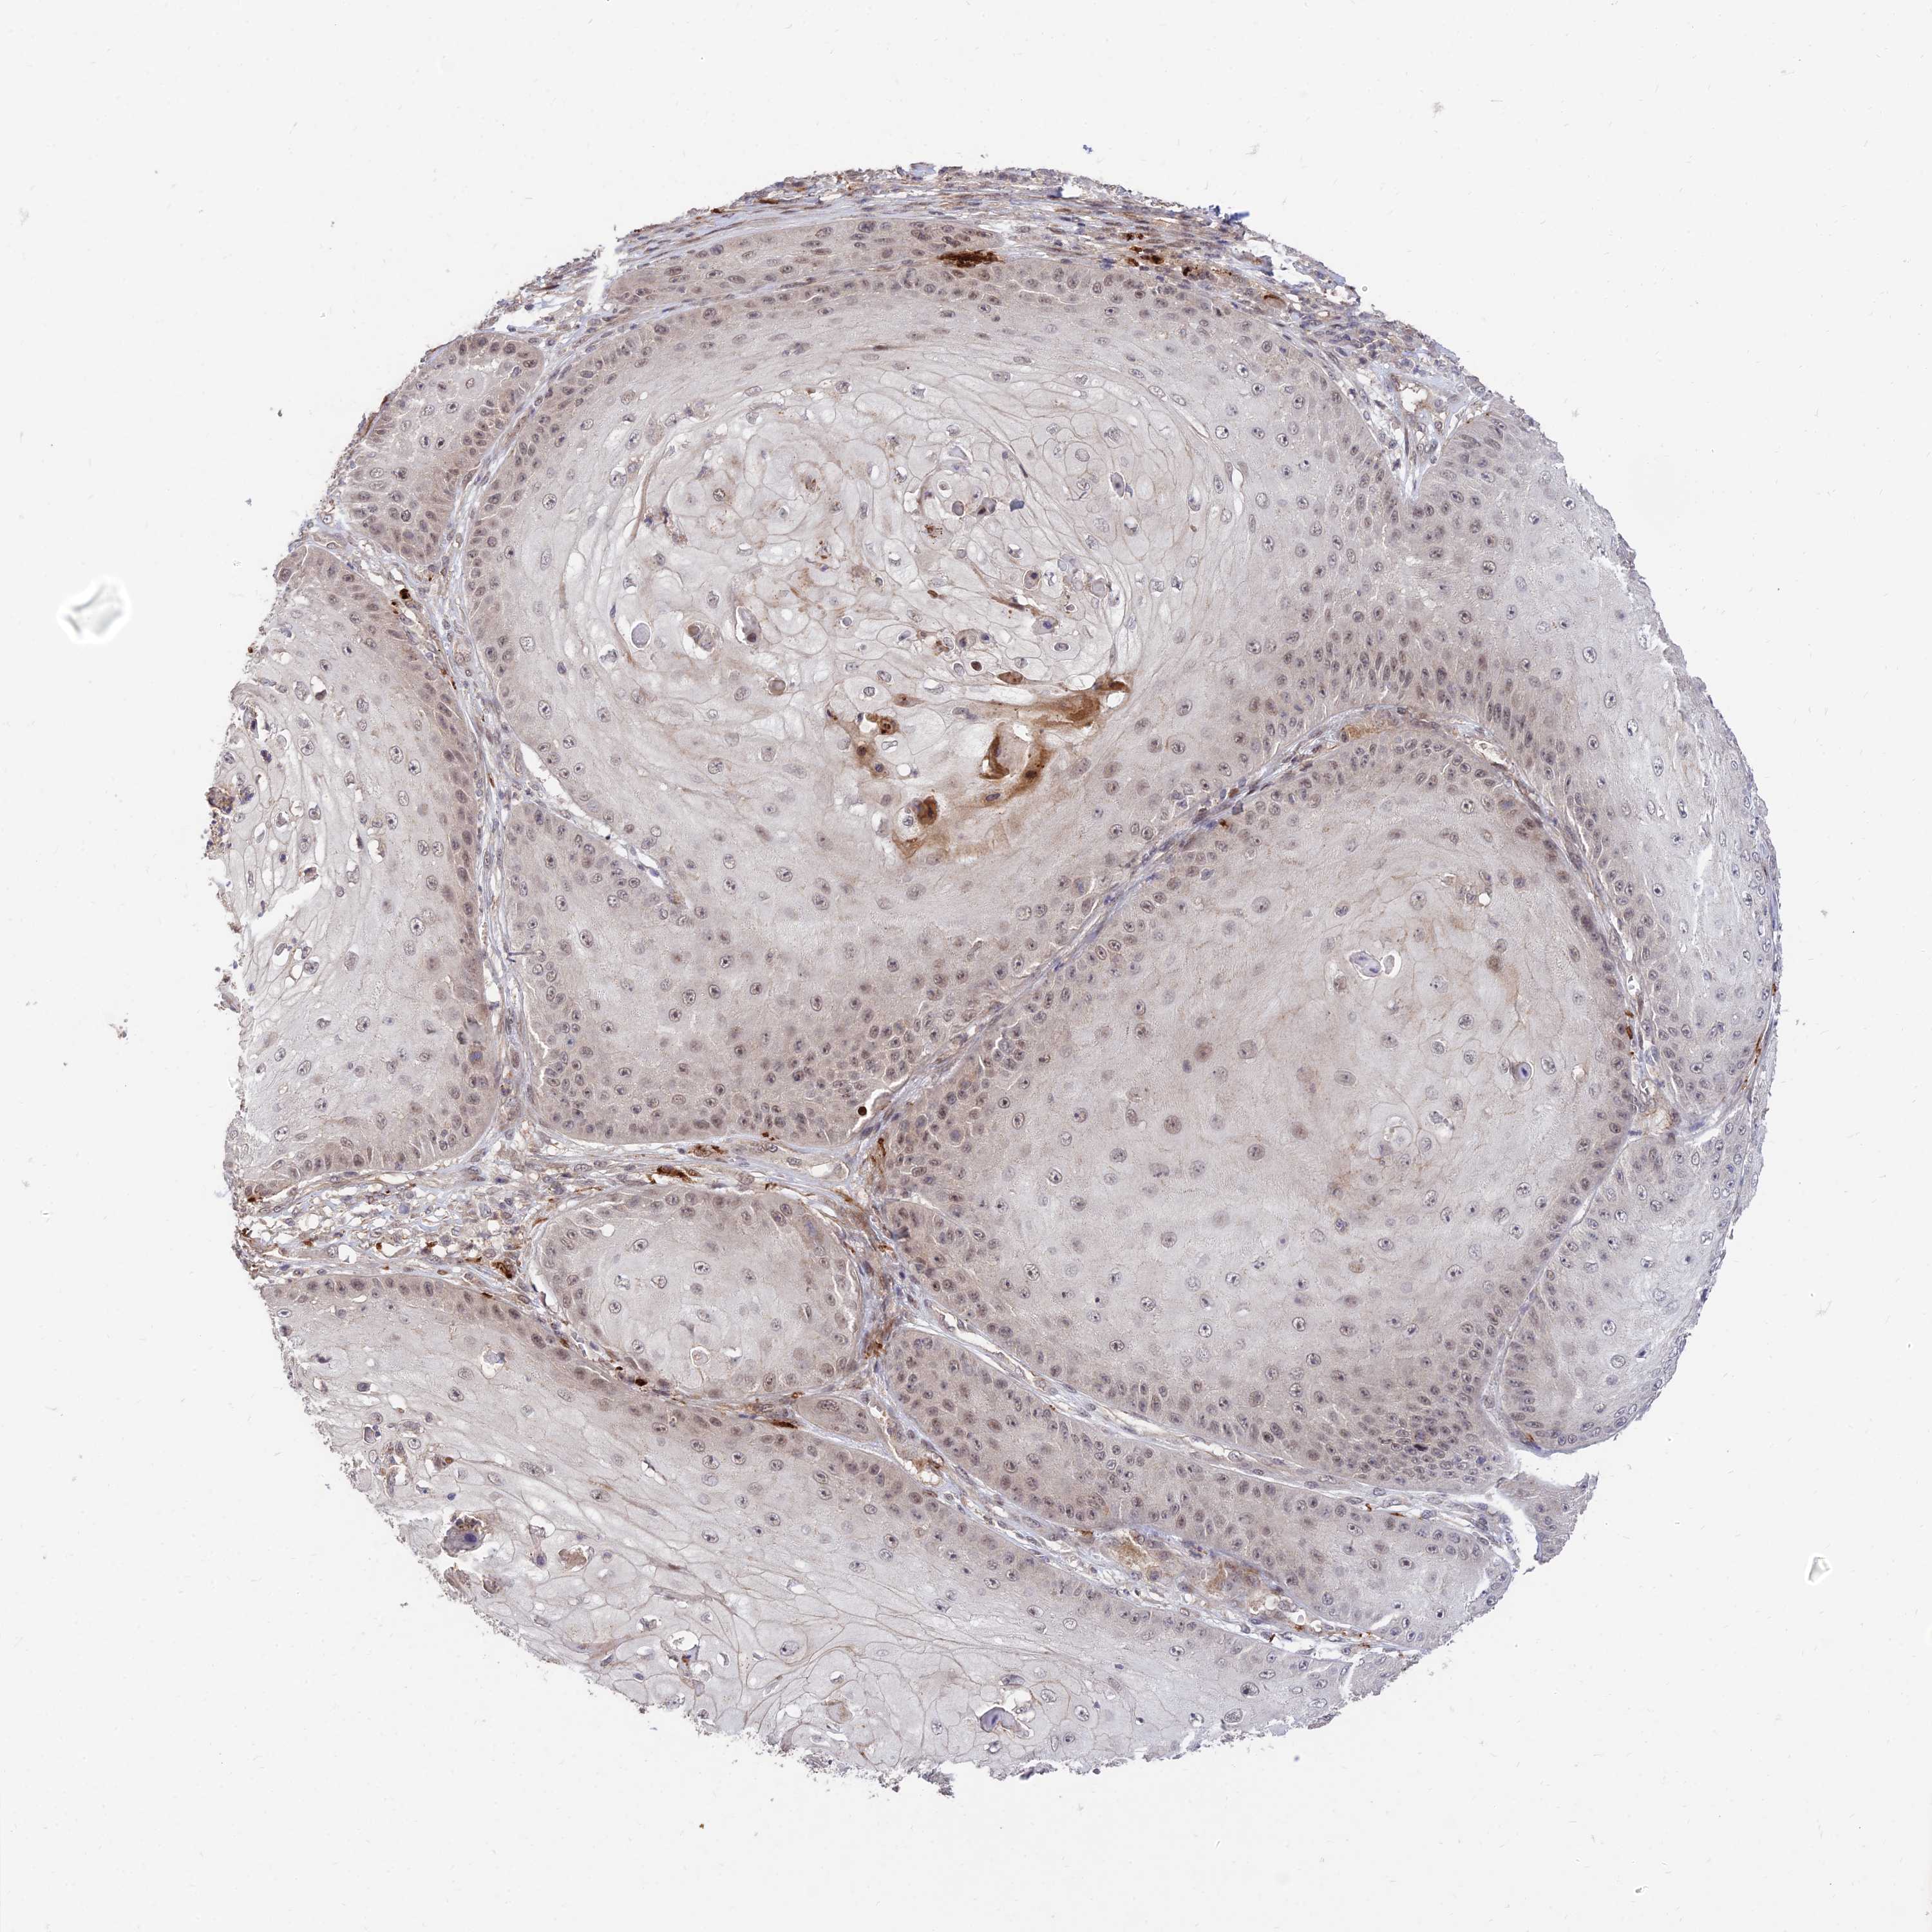

CANCER SKIN CANCER Show tissue menu

Basal cell and squamous cell cancer

SKIN CANCER - Protein expressioni

A mouse-over function shows sample information and annotation data. Click on an image to view it in a full screen mode. Samples can be filtered based on level of antibody staining by selecting one or several of the following categories: high, medium, low and not detected. The assay and annotation is described here.

Each image is clickable and will lead to virtual microscopy that enables deeper exploration of all samples and also displays staining intensity scores, fraction scores and subcellular localization as well as patient and tissue information for each sample.

Antibody HPA044760

Staining

High

Strong

Quantity

Location

Basal cell carcinoma